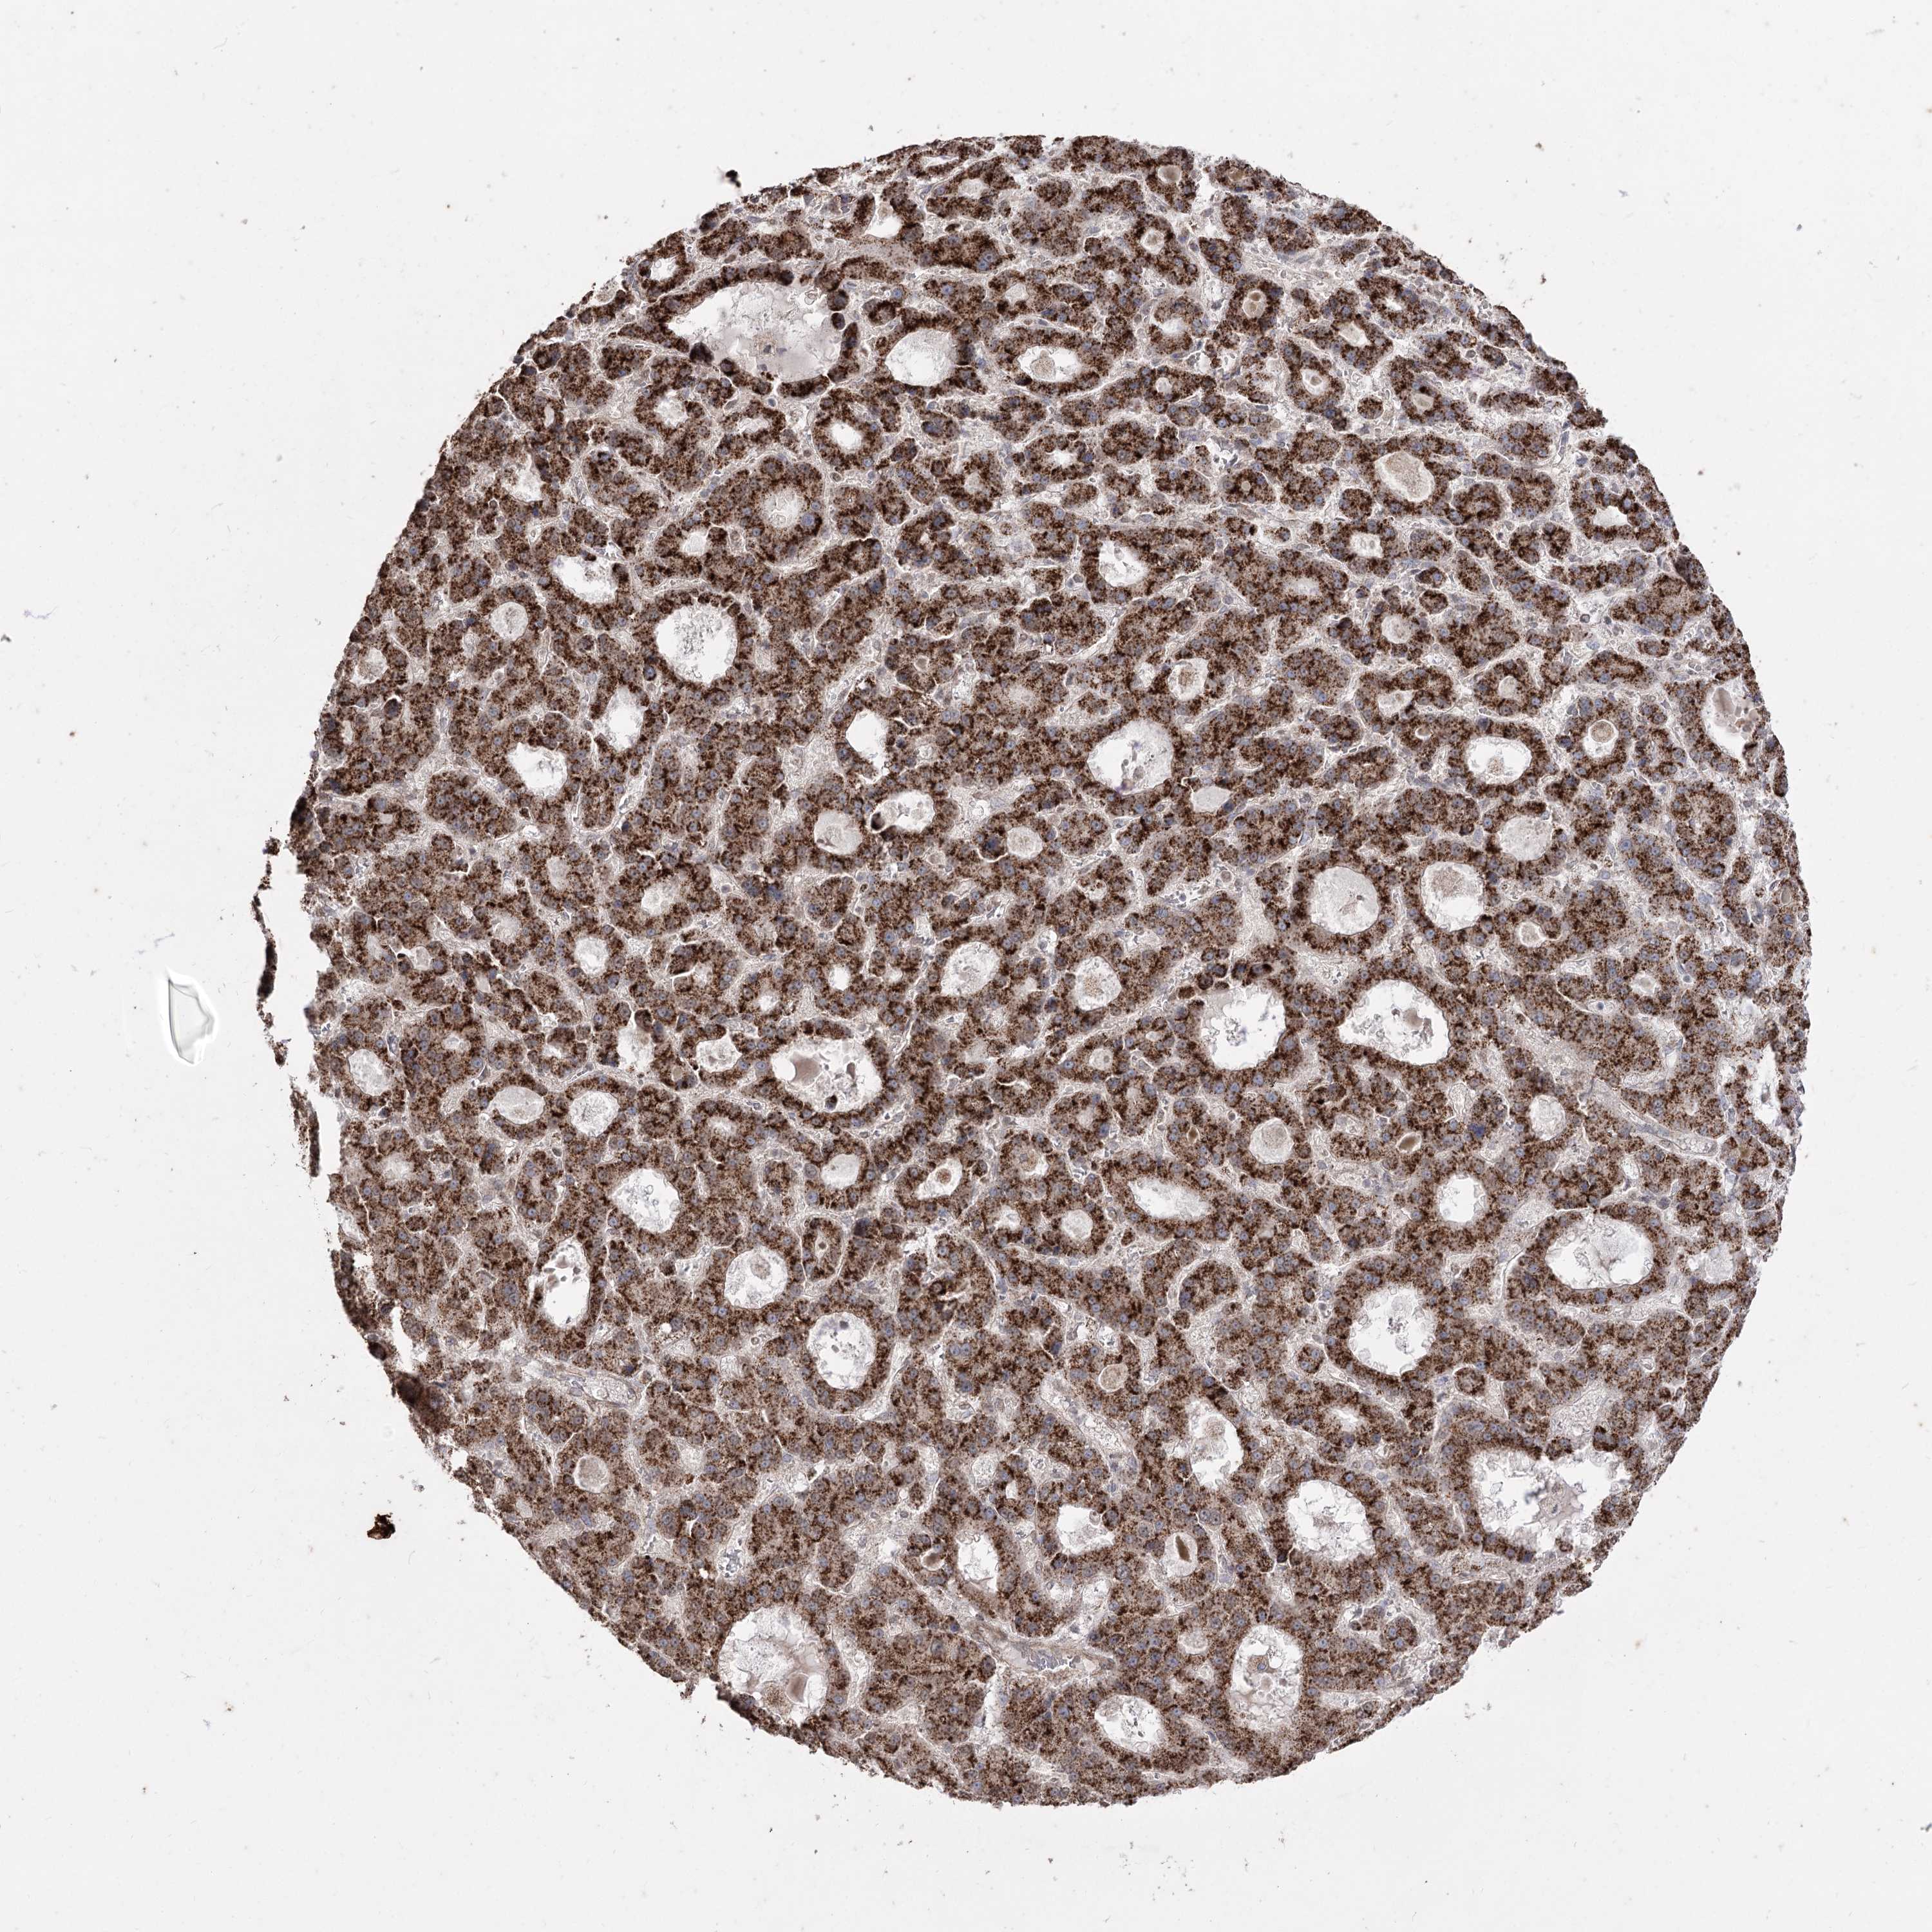

LIVER CANCER - Protein expressioni

A mouse-over function shows sample information and annotation data. Click on an image to view it in a full screen mode. Samples can be filtered based on level of antibody staining by selecting one or several of the following categories: high, medium, low and not detected. The assay and annotation is described here.

Note that samples used for immunohistochemistry by the Human Protein Atlas do not correspond to samples in the TCGA dataset.

Antibody stainingi

Antibody staining in the annotated cell types in the current human tissue is reported as not detected, low, medium, or high, based on conventional immunohistochemistry profiling in selected tissues. This score is based on the combination of the staining intensity and fraction of stained cells.

Each image is clickable and will lead to virtual microscopy that enables deeper exploration of all samples and also displays staining intensity scores, fraction scores and subcellular localization as well as patient and tissue information for each sample.

Antibody HPA035959

Antibody HPA035960

Staining

High

Medium

Low

Not detected

Intensity

Strong

Moderate

Weak

Negative

Quantity

>75%

75%-25%

<25%

None

Location

Nuclear

Cytoplasmic/membranous

Cytoplasmic/membranous,nuclear

Cholangiocarcinoma

Carcinoma, Hepatocellular, NOS